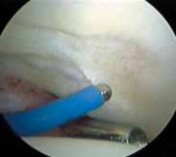

1. Most symptomatic labral tears are managed with selective débridement of the damaged portion ( TECH FIG 1).

2.

Emphasis is given to preserving healthy tissue, because removal of normal labrum can lead to poorer results.

Most labral resection is carried out with a power shaver, debulking the damaged tissue.

1.

Hand instruments and an arthroscopic knife may aid in this resection.

It is important to preserve the healthy tissue but create a stable transition zone when completing the débridement.

A radiofrequency device is especially useful for this because of the limited maneuverability imposed by the architecture of the joint.

TECHNIQUES A B TECH FIG 1 • Arthroscopic view of a right hip from the anterior portal. A. A fragmented labral tear with degeneration within its substance is identified. B. Débridement is initiated with the power shaver. C. A portion of the comminuted labral tear is conservatively stabilized with a radiofrequency probe. D. The damaged portion has been removed, preserving the healthy substance of the C D labrum. LABRAL REPAIR